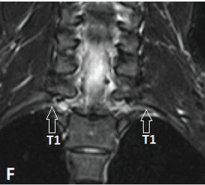

| Figure 1: Normal MR imaging planes and appearance of BP. A-F, Acquisition of the coronal plane with fat-suppressed T2-weighted anterior (D), mid (E), andposterior (F) coronal sections. First a coronal cervical spine scout is obtained (A), based on this a sagittal T2-weighted spin-echo sequence of the cervical spine isacquired (B). Now based on this sagittal image, coronal fat-suppressed T2-weighted and T1-weighted sequences are obtained in a plane parallel to the long axis ofthe lower cervical vertebrae (C) because the BP is oriented in an oblique coronal plane. On coronal fat-suppressed T2-weighted sequence, long axis of the nerveplexus is seen as elongated, uniform calibre, mildly hyperintense fascicular structure. On the anterior coronal image, normal C5, C6, C7 nerve roots (open arrows)are seen on the right side; on the left, the upper (UT), middle (MT) and lower trunks (LT) (solid arrows) are seen (D). At the level of middle scalene muscle (star), onthe mid-section, C8 ventral ramus (open arrows) is seen bilaterally (E), while the T1 nerve root (open arrows) is visualized completely on the posterior section (F). | |